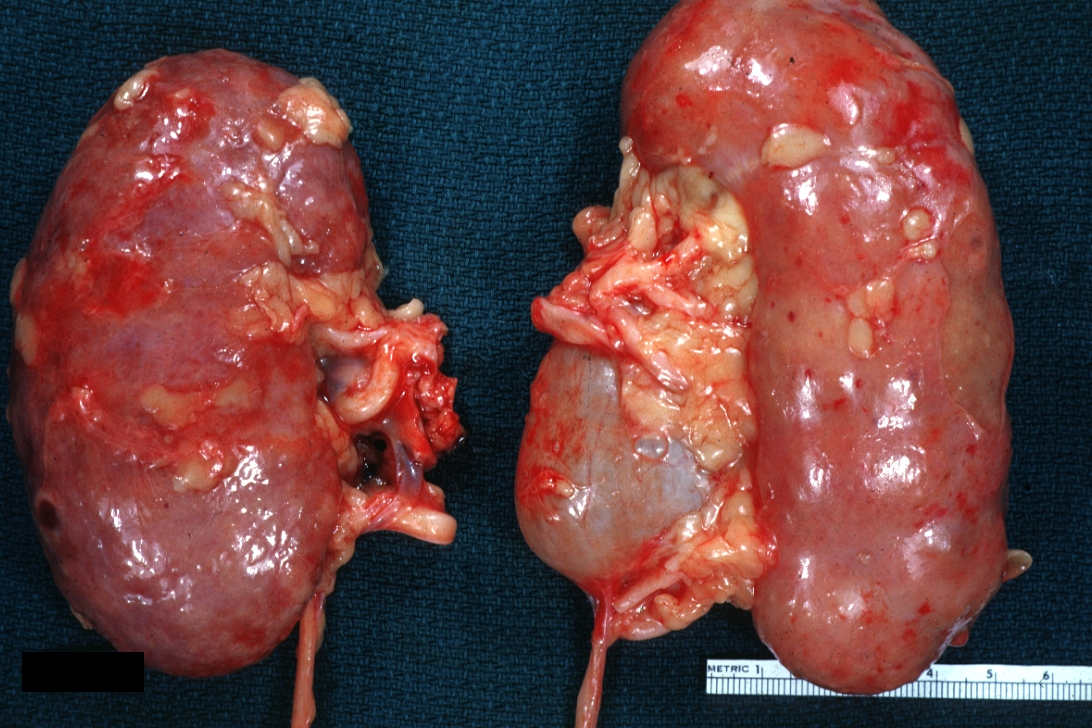

GROSS: Urinary: Kidney: Hydronephrosis: Gross external view of two kidneys one with hydronephrosis good example natural color